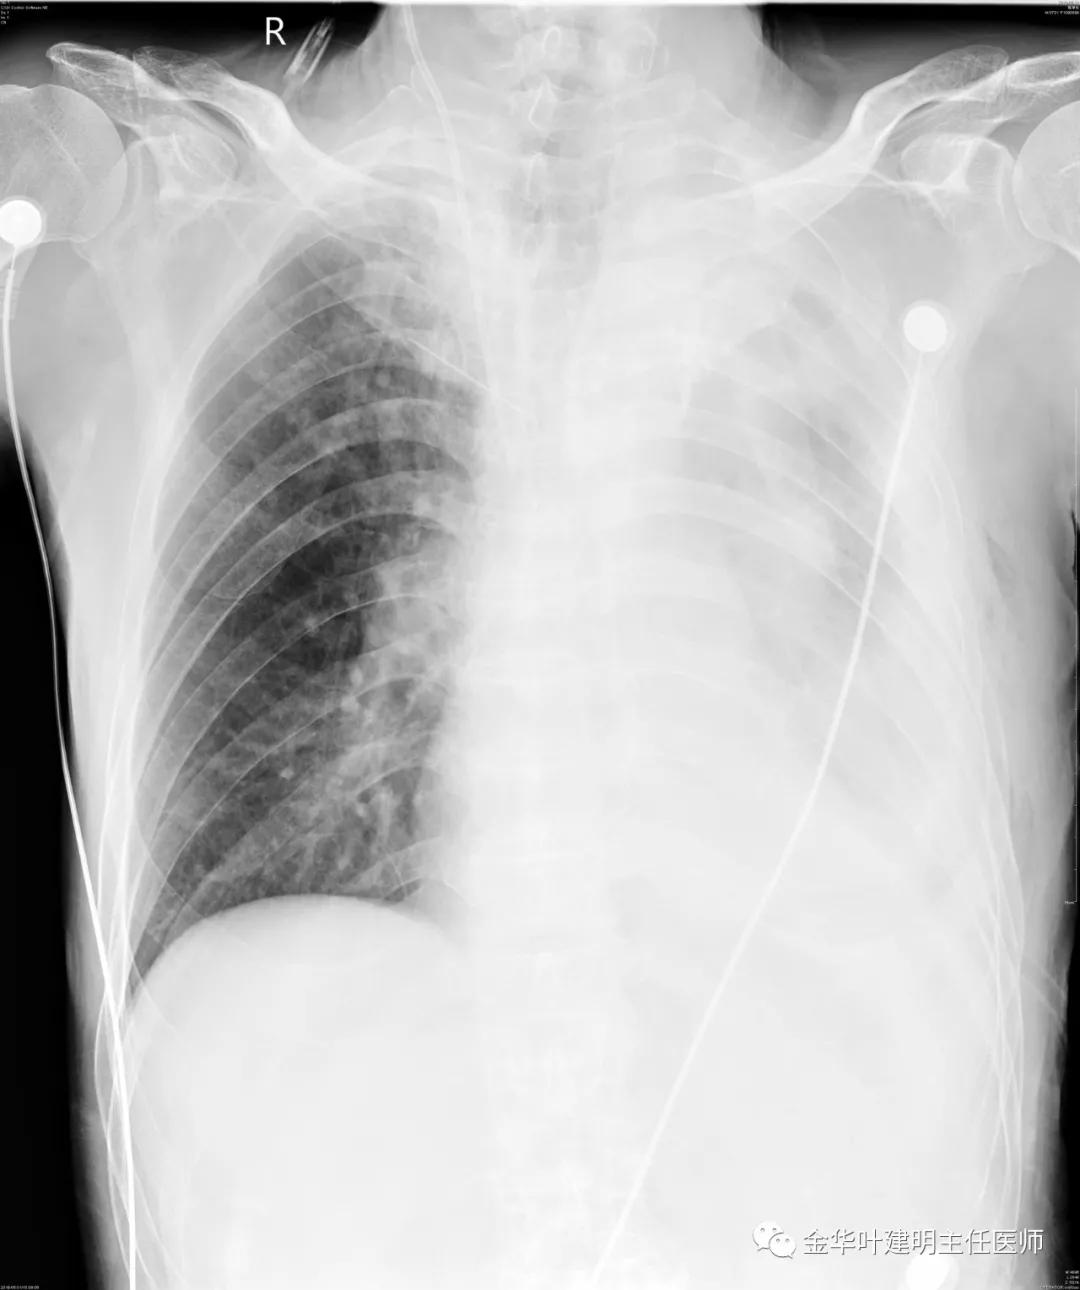

5.31下午7时,从早上开始算胸引700毫升,共900毫升;予以查床边,胸片,结果如下:

考虑左侧大量胸腔积液,遂进一步胸部CT检查:

以上是肺窗表现,下面为纵隔窗影像:

因为引流出的胸液为血性,但感觉不是特别鲜,查血色素9.5 g/L,术前是12.7g/L。当时考虑胸腔内出血可能,较为纠结的是是否需要进胸探查。但鉴于血压正常、心率不快,一般情况良好,不似胸内大出血休克的表现,所以仍想继续观察保守治疗。